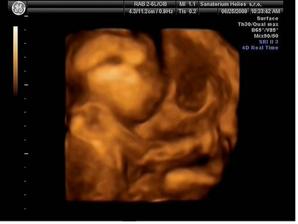

25.6.2009 (24 tt) máme za sebou krásný 3D/4D ultrazvuk v Heliosu. Vše je tak, jak má být :o) A máme definitivně potvrzený pohlaví - je to KLUK - tatínek má důvod k radosti :o) Mimi má 565 g, měří mezi 25 a 30 cm.